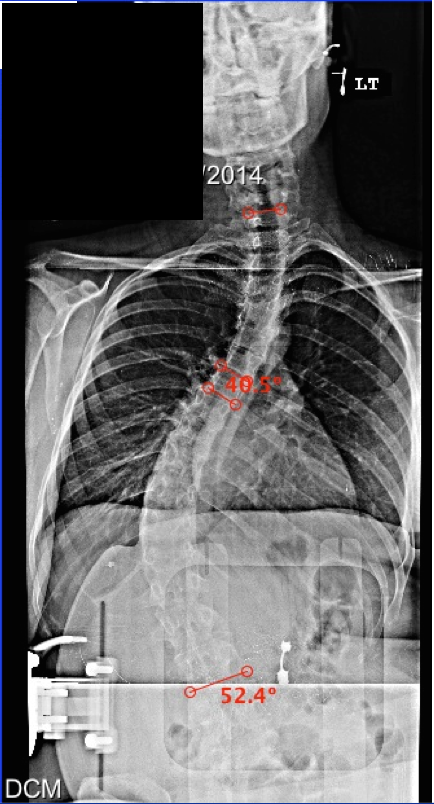

24 year old Mary

came to the Hey Clinic about a year ago with Friedreich’s

ataxia, progressive scoliosis, and back and neck pain. She was first diagnosed with scoliosis

at age 9, but over the past 8 years, her scoliosis progressed almost 5

degrees/year. At the time of her surgery, 6 weeks ago, she had a C6-T7 curve

measuring 40 degrees and a 52 degree curve from T7-L3. In addition, her

kyphosis measured 72 degrees. It was great seeing Mary back in the office

today! Below are Mary's pre-op and post-op x-rays.